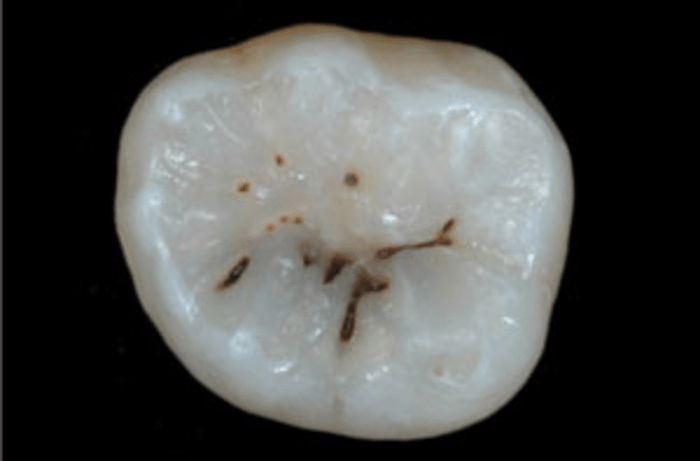

Ранний фиссурный кариес

(один из видов кариеса – по месту локализации)

Выявить фиссурный кариес на раннем этапе, пока он еще мал, сложно. В связи с тем, что фиссуры из-за своего строения практически всегда заполнены зубным налетом, зубными отложениями, которые в большинстве случаев окрашены в темные оттенки, их ошибочно можно признать за кариес фиссур. На самом деле это цвет всего того, что находится в фиссуре. Однако не исключено, что под этой пигментацией может скрываться фиссурный кариес.

Проблема обнаружения фиссурного кариеса объясняется скрытностью протекания кариозного процесса. Зачастую на жевательной поверхности зуба заметна лишь небольшая темная точка (которая может быть скрыта зубными отложениями) в фиссуре зуба, в то время как зуб внутри практически пустой и напоминает электрическую лампочку, где стекло лампочки – это тонкая эмаль зуба, в то время как сам дентин зуба почти разрушен.